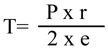

Se ha de tener presente la ley de Laplace: la tensión que debe soportar la pared ha de ser directamente proporcional al radio de la cavidad e inversamente proporcional al espesor de la pared.

El ventrículo izquierdo de estos pacientes ha de soportar mayor tensión debido a:

- Dilatación ventricular (↑ radio).

- Adelgazamiento de la pared ventricular (↓ espesor de la pared).